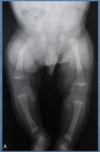

Perfectly

* incurvation des MI * augmentation de l'épaisseur des plaques de croissance * émoussement de l'extrémité des métaphyses * aspect en cupule des métaphyses